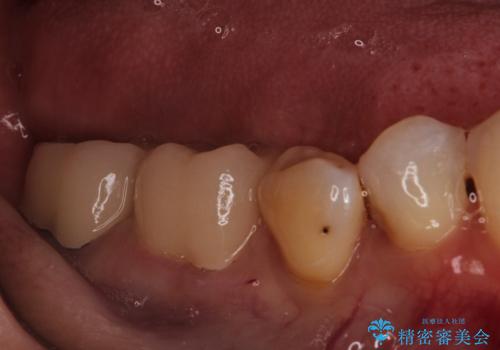

- 他院で治療した被せ物が取れたを主訴に来院された患者様です。被せものが外れた隣の歯もプラスチックの詰め物の劣化や歯に亀裂があったためオールセラミッククランで治療を行いました。

- 242,000円(仮歯11,000円×2本、オールセラミッククラウンスタンダード110,000×2本)費用は治療当時の料金となります

昔詰めたプラスチックの詰め物の範囲が大きいのと破折のリスクや強度の担保のためインレーではなくクラウンで治療を行いました。